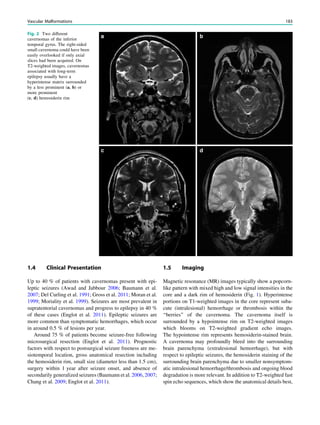

The 2-mm-thick coronal slice

through the hippocampal heads

(d) shows the semicircular canals

in one plane. A small

hyperintense lesion in the white

matter of the parahippocampal